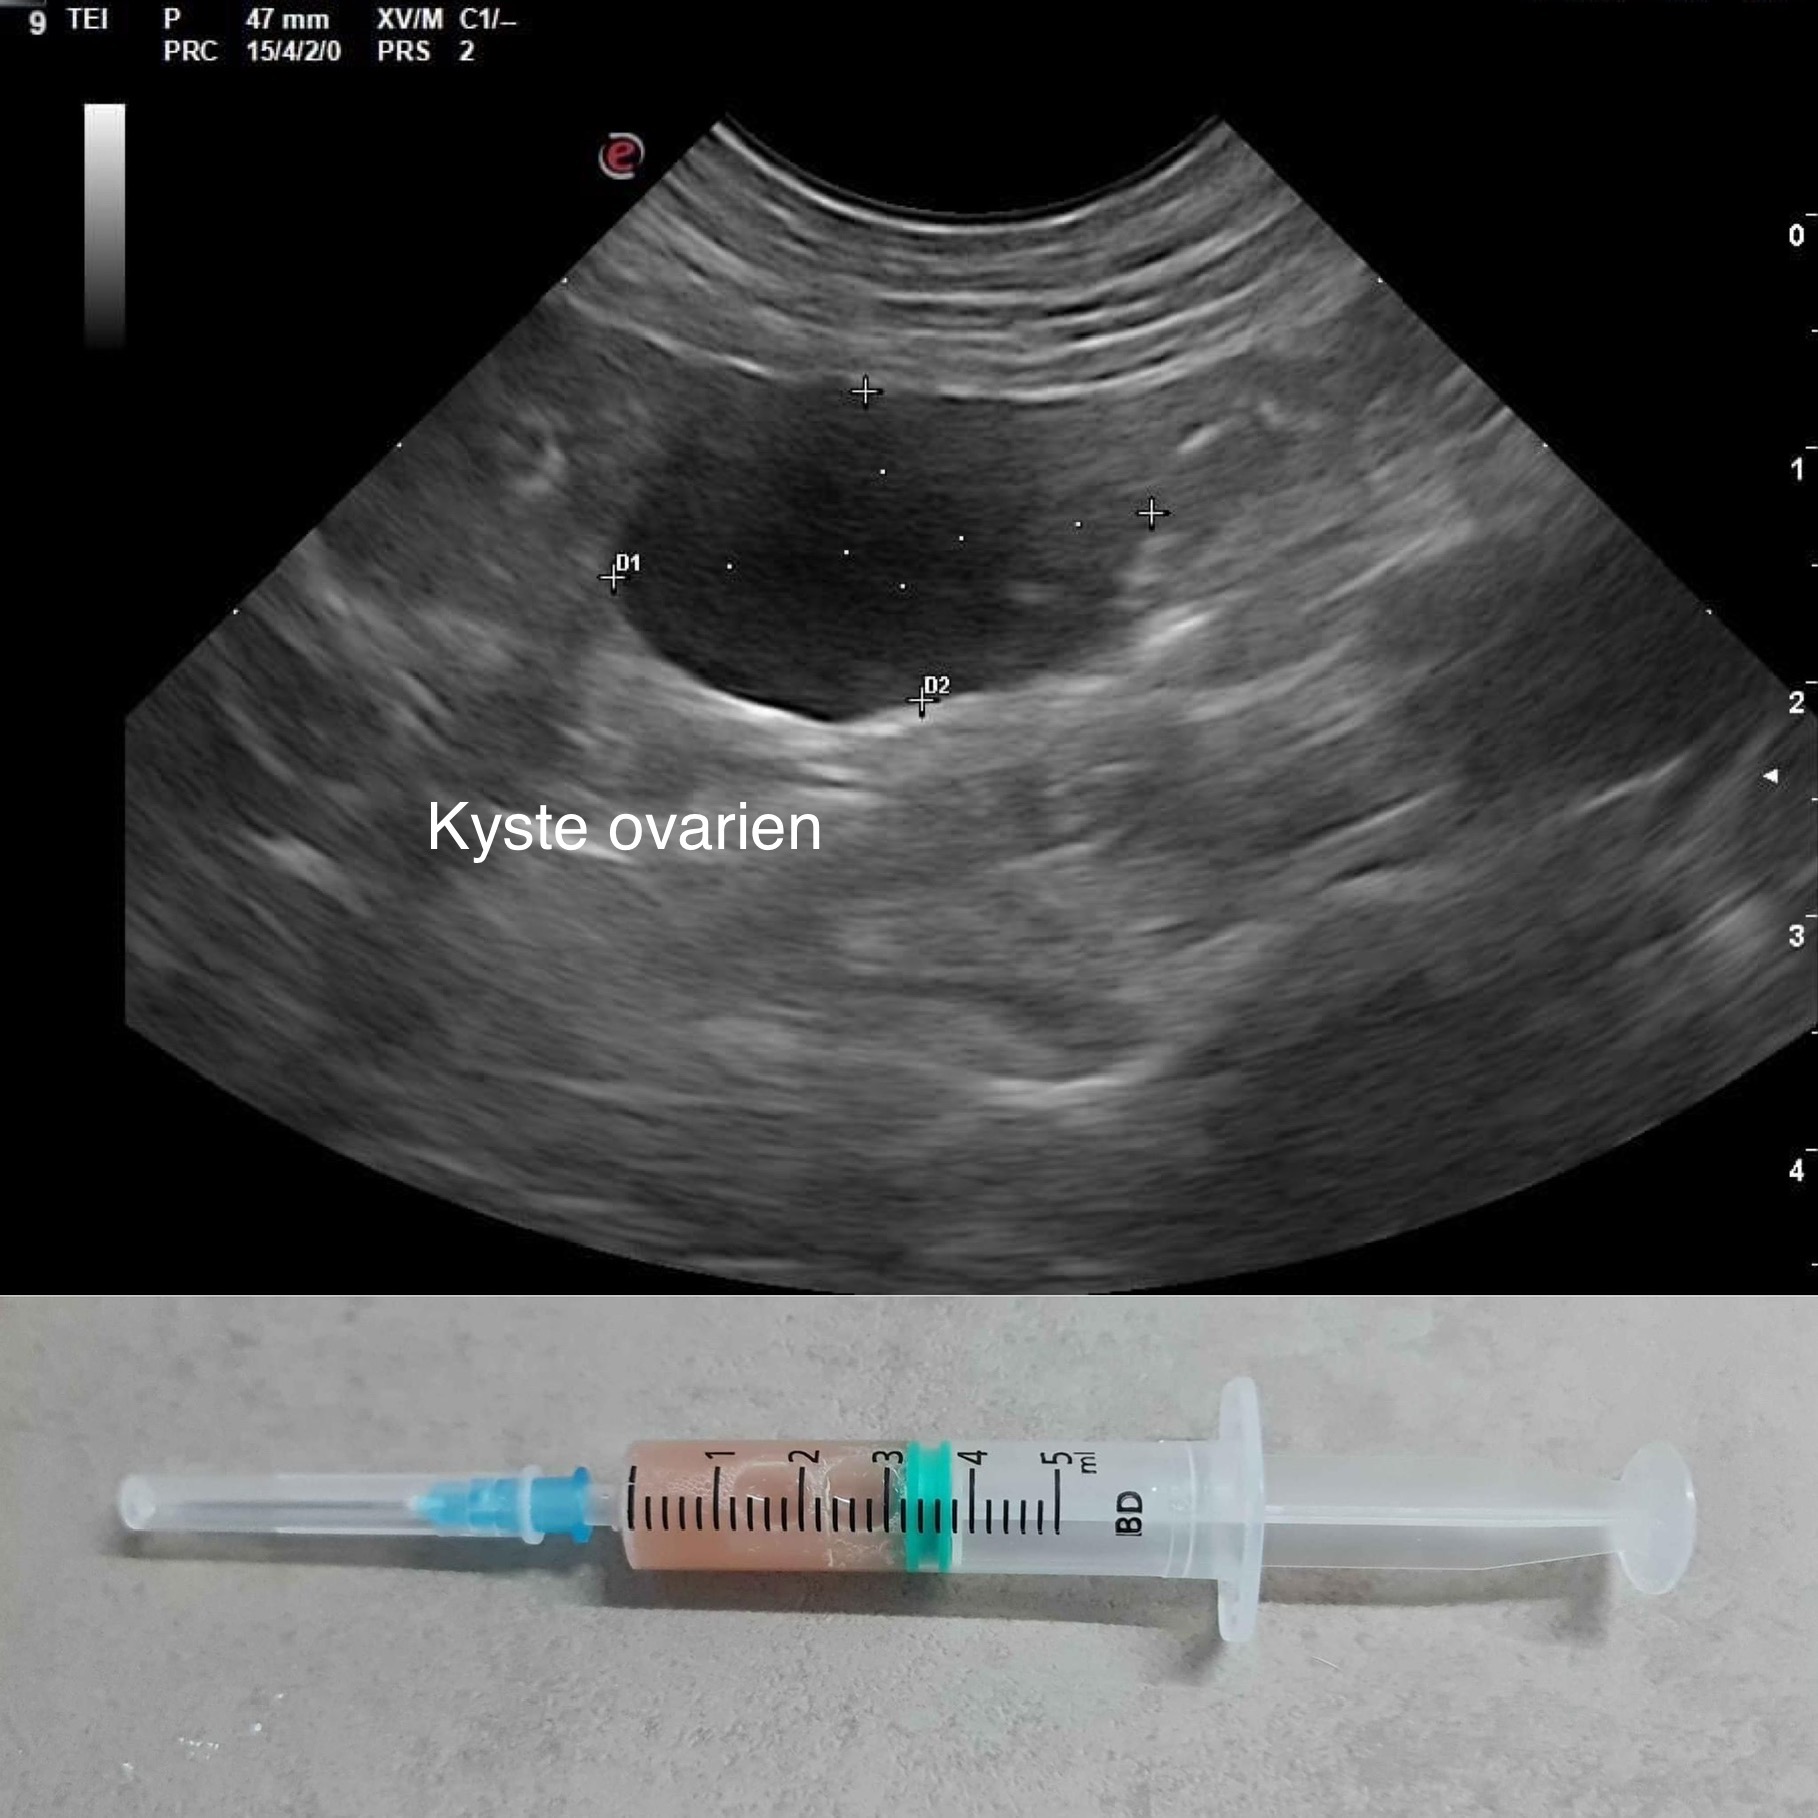

Lors d'avortements répétés ou d'infertilité chez la femelle, des prélèvements vaginaux (bactériologie et recherche quantitative de mycoplasmes), une échographie de l'appareil génital, un bilan hormonal ou un suivi rapproché de la gestation peuvent être indiqués pour établir un diagnostic et vous proposer une prise en charge de votre lice.